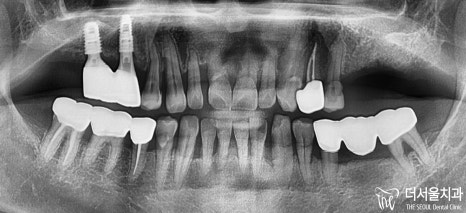

파노라마 엑스레이로 촬영했을때,

염증으로 인한 골소실이

일어나버린 것을 체크할 수 있었구요.

흔들림이 일어날 수밖에 없을 정도로

골소실이 일어난 것을 볼 수 있었습니다.